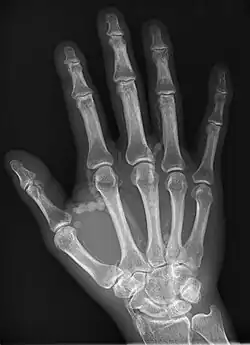

| Hand radiograph showing tumoral calcinosis, PA radiograph of the right hand showing tumoral calcinosis-like metastatic calcification in a patient on dialysis. Dialysis alters calcium phosphate product (>70). Idiopathic tumoral calcinosis is autosomal dominant and is not associated with dialysis. Note the premature arterial calcification which is a clue that this is a renal patient. Vascular calcification contributes to an increase in morbidity. |

Tumoral calcinosis is a rare condition in which there is calcium deposition in the soft tissue in periarticular location, around joints, outside the joint capsule.[1] They are frequently (0.5–3%) seen in patients undergoing renal dialysis. Clinically also known as hyperphosphatemic familial tumoral calcinosis (HFTC), is often caused by genetic mutations in genes that regulate phosphate physiology in the body (leading to too much phosphate (hyperphosphatemia)). Best described genes that harbour mutations in humans are FGF-23,[2] Klotho (KL),[3] or GALNT3.[4] A zebrafish animal model with reduced GALNT3 expression also showed HFTC-like phenotype,[5] indicating an evolutionary conserved mechanism that is involved in developing tumoral calcinosis.

The name indicates calcinosis (calcium deposition) which resembles tumor (like a new growth). They are not true neoplasms – they don't have dividing cells. They are just deposition of inorganic calcium with serum exudate. Children and adolescents (6 to 25 years) are the most commonly affected. The symptom that the accumulations cause is not pain but swelling around joints. They have propensity to enlarge progressively and ulcerate the overlying skin and extrude. They are most common around shoulders, hips and elbows. Laboratory evaluation reveal normal serum calcium levels and hyperphosphatemia. Rarely ALP (alkaline phosphatase – an enzyme active at sites of bone formation) may be elevated. Treatment is normalization of serum phosphate levels and resection of lesions. Surgical removal should be complete and if part of it is left, recurrence is likely to occur. Cutting through the excised calcium deposition reveals semifluid calcium suspension in albumin encapsulated by fibrous tissue.